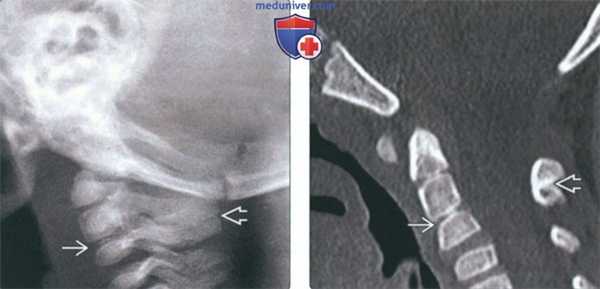

(Слева) На рентгенограмме шейного отдела позвоночника (СКФ II типа) в боковой проекции определяется нарушение сегментации С2-С3 в с наличием рудиментарного межпозвонковою диска и со слиянием остистых отроет-ков С2 и СЗ.

(Справа) На сагиттальной КТ (СКФ II типа) определяется классическое нарушение сегментации С2-С3 с типичным рудиментарным межпозвонковым диском. Также определяется нарушение сегментации остистых отростков С2 и СЗ.